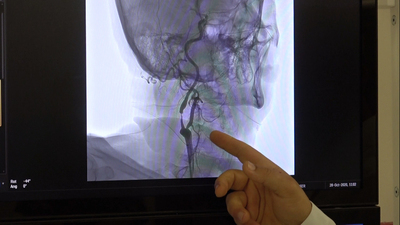

Adana Şehir Eğitim ve Araştırma Hastanesi İnme Merkezi Sorumlusu Nöroloji Uzmanı Prof. Dr. Zülfikar Arlıer, beyin damarının yırtılmasına bağlı, beynin kafatası ile iç zarı ya da iç zar ve beyin arasında olabilen beyin kanamalarının ameliyatla tedavi edilebildiğini ancak baloncuķ veya doğumsal damar bozukluklarının ilerleyen teknolojiyle ameliyata gerek kalmadan anjiyo yöntemiyle önlenebildiğini belirtti.

Beyin kanamalarının önlenebilir olduğuna vurgu yapan Prof. Dr. Arlıer, şöyle konuştu: "Beyin kanamaları genellikle tansiyon, travma, tümör, baloncuk gibi durumlar ya da genetik olarak beyin damarlarının zayıf olmasına bağlı zamanla yırtılmasıyla oluşan kanamalardır. Eğer tansiyona bağlı bir durum ise tansiyonun ayarlanması, diyet yapılması, tuzsuz beslenilmesiyle önlenebilir. Beyin damarlarının zayıflamasıyla oluşan baloncuk dediğimiz kanamalarda ise MR, tomografi gibi filmlerle önceden tespit edilebilirse ameliyat ya da anjiyo yöntemiyle kasıktan girilip, beyin damarındaki o baloncuğun ya da bozuk damarların içi özel maddelerle doldurularak önlenebilir. Genetik olarak zayıf ya da karmaşık damar yapısına bağlı kanamalar da ameliyatla veya anjiyo yöntemiyle yine kapatılarak o damarlardaki basınçlar düşürülüp kanama önlenebilir."

"Özellikle baloncuk ya da doğumsal damar bozukluklarından kaynaklı kanamalar, daha önceden tespit edilemiyordu ya da ameliyat dışında başka hiçbir çözüm yoktu ama günümüzde artık teknolojik gelişmelerle beyni açmadan, kasıktan girilerek o damarlara kadar ulaşıp özel sıvı veya özel maddelerle damar tedavi edilerek önlenebiliyor. Bu son 10-15 yılın teknolojisi ama her geçen gün gelişen bir teknoloji. Özellikle son 5 yılda ameliyattan ziyade uygun damarlarda anjiyo ile kapatma yöntemleri ön planda."